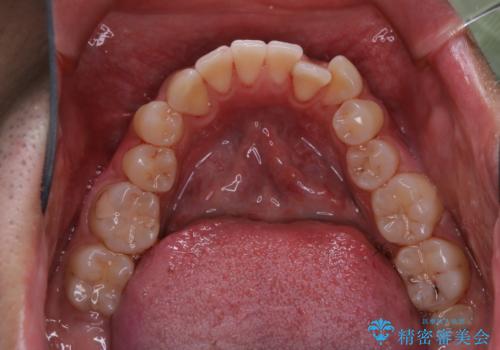

バイオフィルムやステインを取り除くと、ご自身本来の歯の色となります。

施術後はとてもスッキリとした爽快感が得られ、定期的に行うことで、虫歯・歯周病・口臭予防にもなります。